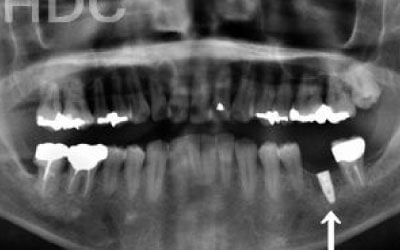

骨が薄い場合は、そのままインプラントすることはお勧めできません。

ただ、事前に骨を増やす治療をしたり、インプラントと同時に骨を増やす治療をしたりすればインプラントをすることは可能です。